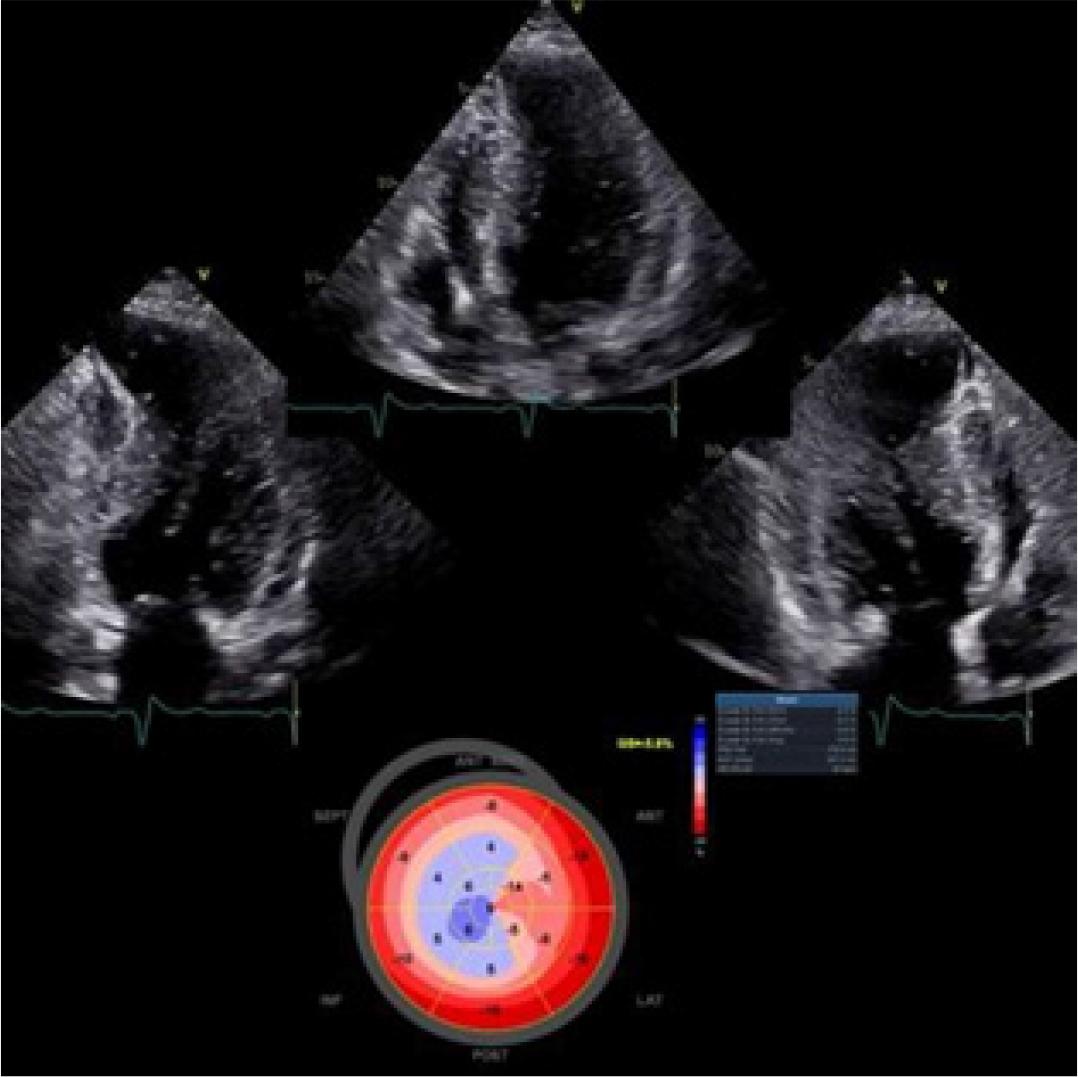

Figure 2